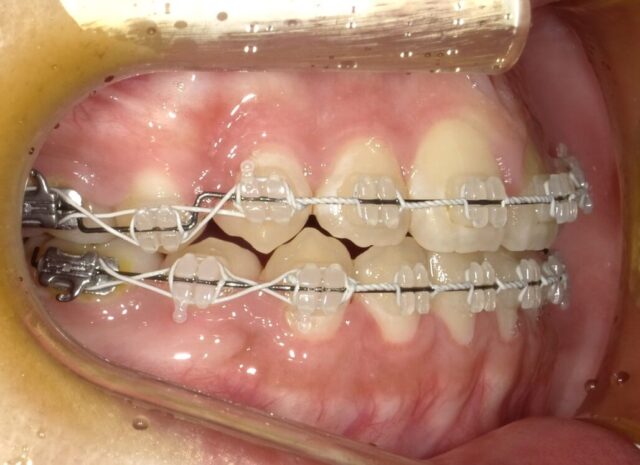

≪右側面観≫

2023年5月

2023年6月

2023年7月

2023年8月

2023年9月

2023年10月

2023年11月

2023年12月

2024年1月

2024年2月

2024年3月

2024年4月

2024年5月

2024年6月

2024年7月

2024年8月

2024年9月

2024年10月

2024年12月

2025年1月